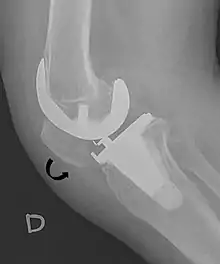

- ↑ Melloni, Pietro; Veintemillas, Maite; Marin, Anna; Valls, Rafael (2013). "Imaging Patellar Complications After Knee Arthroplasty". Arthroplasty - Update. doi:10.5772/53666. ISBN 978-953-51-0995-2. (CC-BY-3.0)